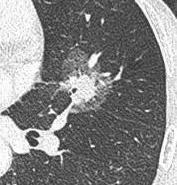

结节长相:肺内密度轻微增加,增加程度小于实性改变,呈模糊的云雾状,并可见其内血管和支气管纹理。

产生原因:根据肺部磨玻璃影内部成分均一程度的不同,磨玻璃结节又可分为单纯磨玻璃结节及混合型磨玻璃结节。造成磨玻璃结节的原因包括感染性病变、肿瘤等多方面。